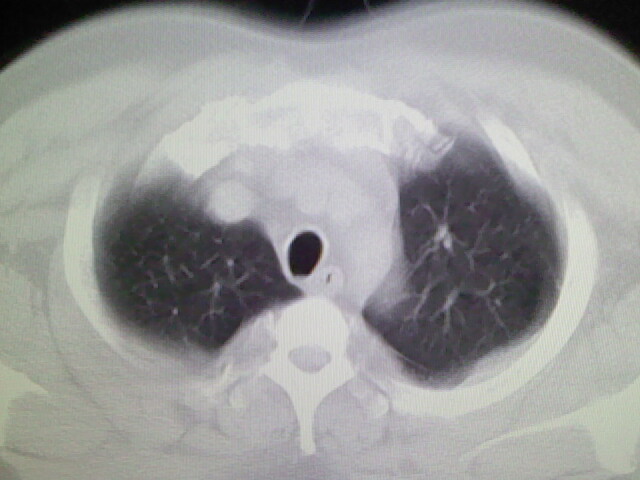

左上肺局限片状透光度增强区,肺纹理稀少,可考虑局限性肺气肿。

左上肺局限性肺透光度减低,肺纹理稀少;这虽然符合早期肺栓塞的改变,但与局限性肺气肿难以鉴别。

书上讲早期肺栓塞就是表现肺透光度减低,肺纹稀少。